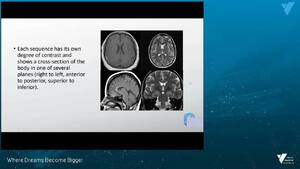

- Differentiate between different radiological modalities.

- Know the common terminology used in describing in different radiological modalities.